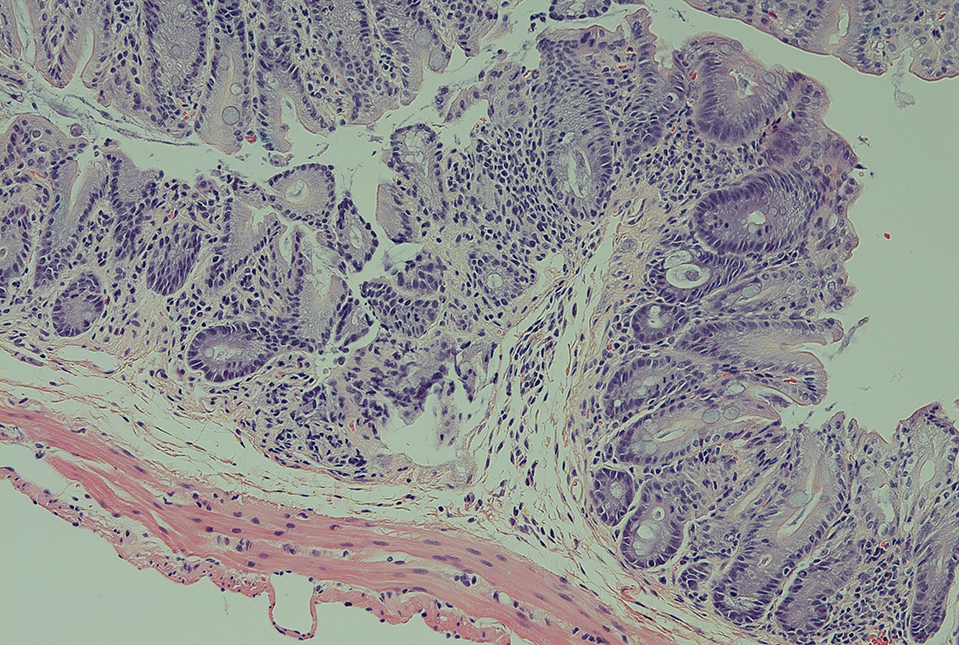

To their surprise, the scientists found that a high level of STING signaling, driven by a generally inflammatory gut environment, also reverses immune tolerance—by killing the ILC3s. In collaboration with the Roberts Institute for Research in IBD Live Cell Bank, the researchers found evidence of this overactive STING signaling, and ILC3 depletion, in gut tissue from patients with inflammatory bowel disease.